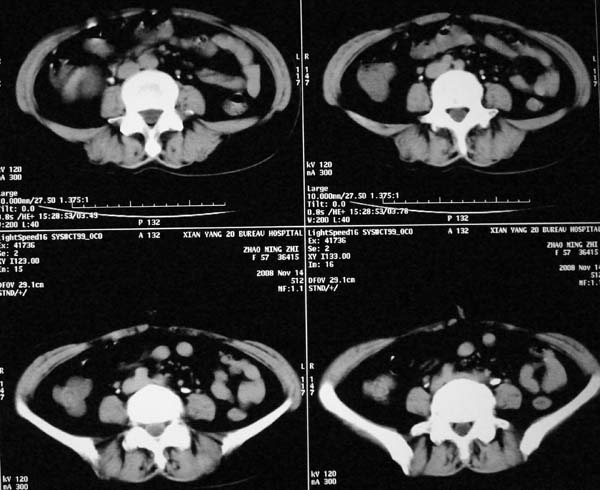

以下是引用dr.yang在2008-11-9 21:56:00的发言:[br]右肾上极占位?建议增强

以下是引用x-man在2008-11-9 22:30:00的发言:[br]建议先增强,右肾影明显增大,上极见边不清低密度肿块影,肿瘤待定.

以下是引用卜一在2008-11-10 8:09:00的发言:[br]建议先增强,右肾影明显增大,上极见边不清低密度肿块影,肿瘤待定.支持!另:第一次碎石是否肾受到损伤?合并感染?不知第一次碎石前是否做过彩超?

以下是引用dsl555在2008-11-9 23:57:00的发言:[br]建议先增强,右肾影明显增大,上极见边不清低密度肿块影,肿瘤待定. [br] [br]